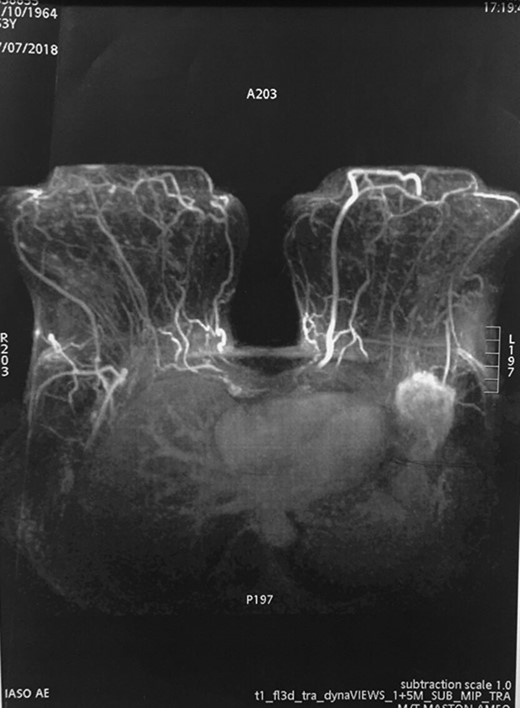

Following these, mammography was performed but it was not helpful due to the location of the mass. The breast ultrasound (U/S) and the U/S of the axilla detected a hypoechoic mass in the axillary fossa. MRI was also conducted, confirming a single lesion in the left axilla. There were no additional lesions seen in the same or contralateral breast on MRI (Fig. 1). Subsequent core needle biopsy (FNAB) established the diagnosis of breast infiltrating ductal carcinoma (Not otherwise specified), grade 2. Based on this a decision was made to proceed to quadrantectomy.During the surgery, the tumor was detected superficial to the clavipectoral fascia (Figs 2–4). A quadrantectomy was performed along with axillary lymph node block dissection since the sentinel node was positive for metastasis. The rest of the operation continued in the usual fashion. A drain was placed at the end of the procedure. The post-operative recovery was uneventful. The patient was discharged five days after the surgery, when the drain was finally removed.

MRI detected the tumor in the left axilla. However, it cannot clarify whether the tumor is part of the tail of Spence or metastasis of the axillary lymph nodes.